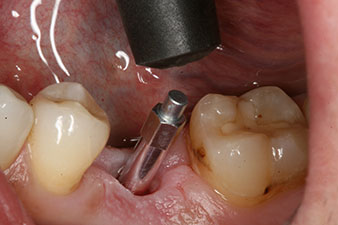

After healing of the soft tissue, the implant stability was measured again before delivery of the prosthetic restoration.

Both values were virtually unchanged and were between the medium and the high range – where the lower value is always used as the reference value that determines the treatment.

Therefore, successful osseointegration and adequate biological stability could be recorded, which enabled an impression to be taken in the same session.

The implant stability is better described as micromobility and is best measured by resonance-frequency analysis (RFA) (7, 8). Measurements are best made in two directions, as in the case study (9). The technology is optionally available as a module that can be docked to the Implantmed implantology motor. A separate device is not required. The lower value is always applicable for the therapy. Measured values are displayed on the touch screen of the implantology motor as the implant-stability quotient (ISQ). Along with the torque curve for insertion and data on preparation of the implant bed, they can be recorded on a USB stick and used for documentation for the patient and the implant. Overall, it is a very user-friendly and reliable technology for everyday work in implantology, particularly in combination with the W&H Implantmed.